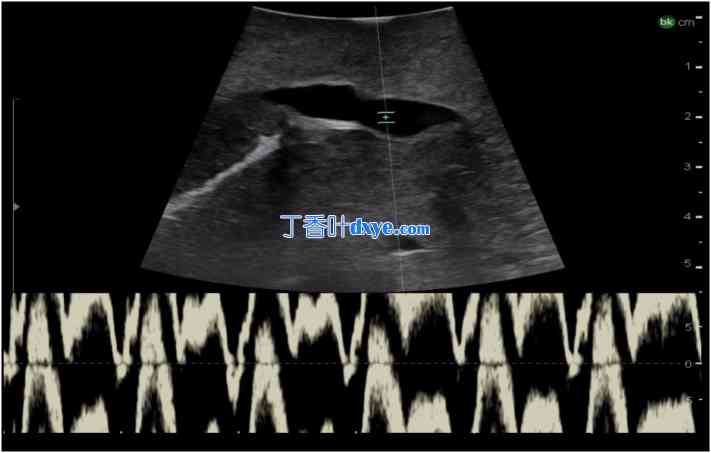

16.jpg

图 16

门静脉分叉处的术中超声检查。a) 横向探头放置和超声图像,b) 纵向探头放置和超声图像。

MPV 主门静脉、LPV 左门静脉、RPV 右门静脉、MHV 中肝静脉支流、HD 胆管、HA 肝动脉、C 尾状核。